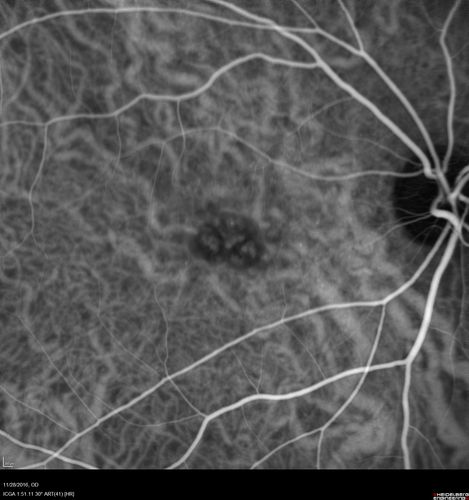

Confluent Soft Drusen with Subetinal Fluid - Right Eye

Asymptomatic 85 year old man.  OCT shows pocket of subfoveal fluid in the center of the macula.  This could be mechanical from the drusen preventing the retina from settling down.  Testing did not reveal a CNVM and subsequent OCT 6 weeks later showed no change in structure.